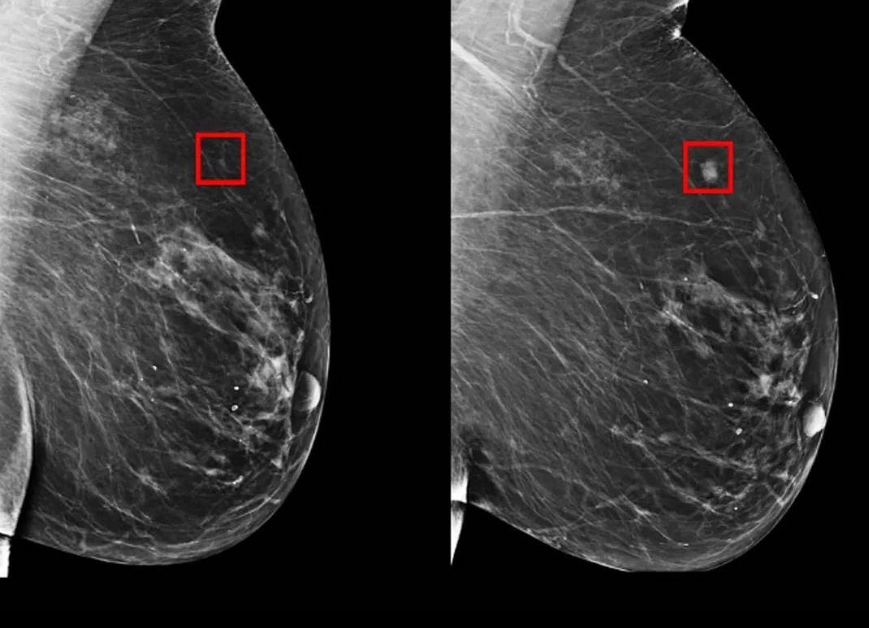

La Inteligencia Artificial (IA) ha demostrado ser una herramienta increíblemente poderosa en diversos campos, y la medicina no es la excepción. Uno de los avances más emocionantes es su capacidad para detectar el cáncer de mama hasta cinco años antes de que se desarrolle. Gracias a la colaboración entre los investigadores del MIT y el Hospital General de Massachusetts, un nuevo modelo predictivo ha surgido, ofreciendo una esperanza renovada en la lucha contra esta enfermedad debilitante.

Los investigadores se basaron en una gran cantidad de datos para desarrollar su modelo predictivo. Utilizando mamografías recopiladas entre 2009 y 2012, provenientes de más de 6,000 pacientes del Hospital General de Massachusetts, se estableció una base sólida para el análisis. Esta vasta colección de datos permitió a la IA buscar patrones y sutilezas que los ojos humanos no podrían haber percibido.

La Inteligencia Artificial: Descifrando Patrones Sutiles

El corazón de este avance radica en la capacidad de la IA para detectar patrones sutiles en los tejidos mamarios. Estos patrones no serían identificables por radiólogos y especialistas humanos, pero la IA puede analizar datos a una escala que va más allá de las capacidades humanas. La IA se sumerge en los detalles, identificando anomalías microscópicas que podrían estar relacionadas con el desarrollo futuro del cáncer de mama.

1. ¿Cómo funciona la Inteligencia Artificial en la detección del cáncer de mama? La IA analiza patrones sutiles en las mamografías que los médicos no pueden percibir, permitiendo la predicción del cáncer hasta cinco años antes de su desarrollo.